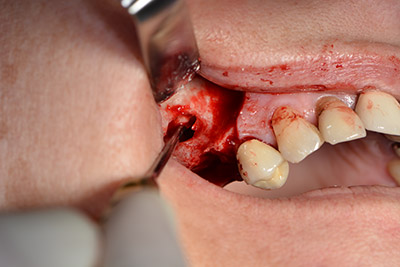

The next step was the sinus floor elevation with simultaneous implantation. The Implantmed also had a presetting at the first position for the buccal fenestration of the maxillary sinus wall.

The fenestration was prepared at 35,000 rpm and then the nasal mucosa were prepared in the cranial direction (Fig. 13 to 14).

The implant was then placed and the bone built up. In this case, because of the size of the augmentation region, autologous bone chips, harvested with an osseous trap as drilling chips from implantation 16 and fenestration 14, were mixed with bone replacement material.